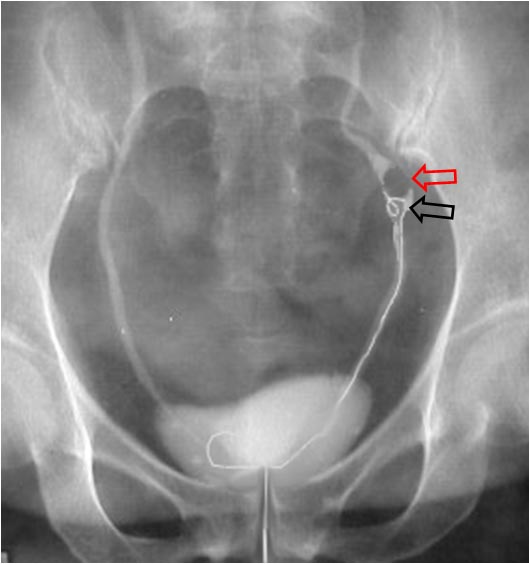

SIGNO DEL CHORRO O JET URETERAL INVERTIDO

Signo de crecimiento prostático en la fase excretora precoz de la urografía intravenosa. El crecimiento prostático provoca el levantamiento de los orificios de entrada de los uréteres a la vejiga y hace que el jet ureteral sea dirigido hacia arriba en vez de hacia abajo.

En la imagen vemos una gran hipertrofia prostática que levanta el suelo vesical (flecha negra) y altera la entrada de ambos uréteres (flechas rojas), si bien no vemos el jet.